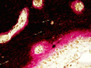

Our skull may look and feel solid but it's actually made up of 28 separate bones that fuse together during development. Having multiple junctions allows the skull to squeeze through the birth canal and then keep up with rapid brain growth. If this process is not perfectly orchestrated, however, children can be born with serious deformations. Cleft palates, which affect one in 700 newborns, are a case in point, caused when the two arch-like plates in the roof of their mouth fail to come together in the womb. Left with a hole in their palate, children can develop speech and feeding problems. The central pin-shaped blue region shows this gap in the skull of a mouse lacking a specific protein implicated in palate formation. In healthy animals with this protein, this space does not exist as the surrounding bones (coloured in pink) close in and fuse together before birth.